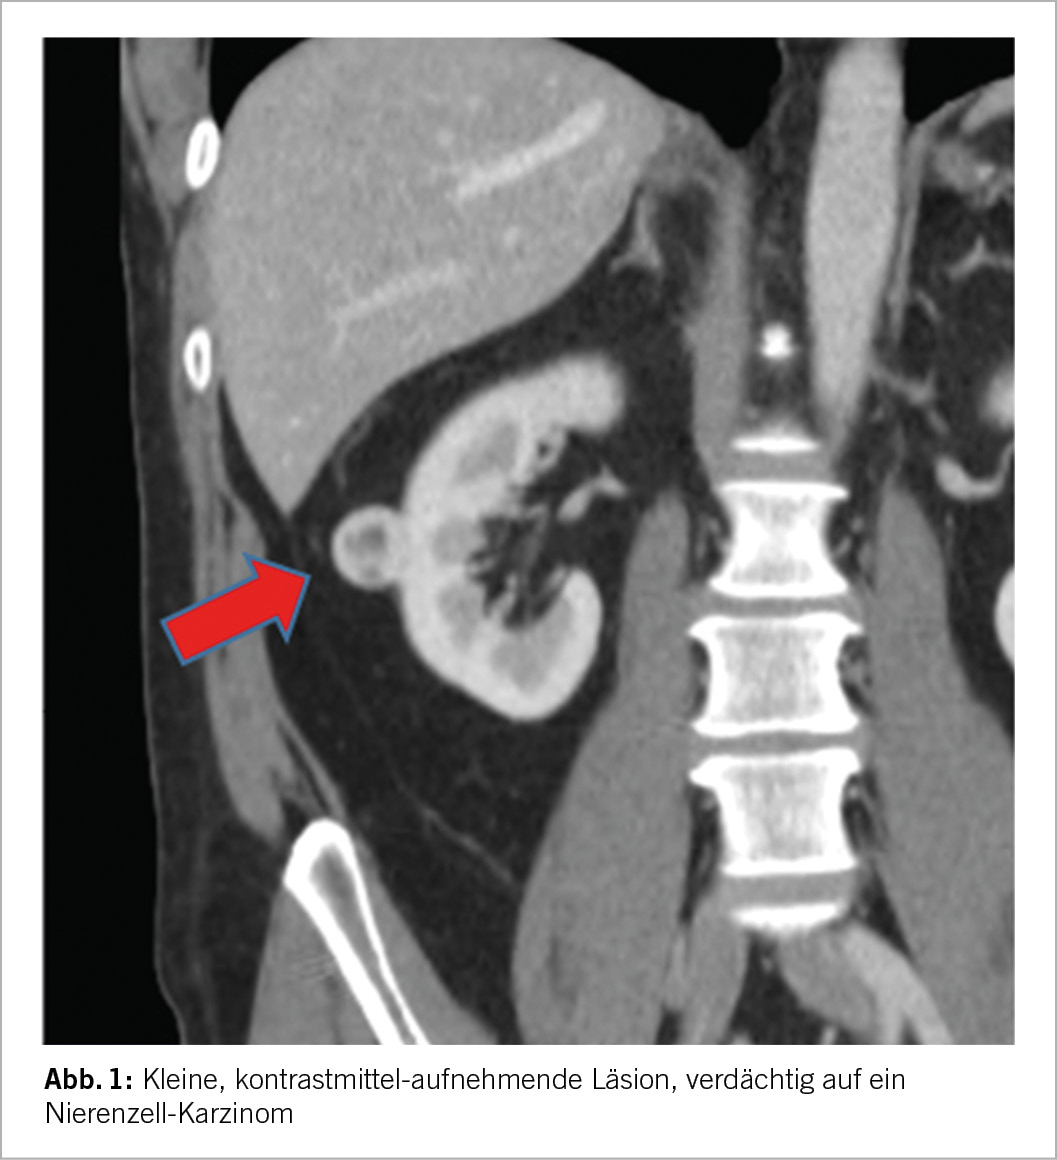

Die bildgebende Grundlage für die Beurteilung einer SRM ist entweder eine qualitativ hochwertige CT oder MRI-Untersuchung nativ sowie mit Kontrastmittel. Beide Verfahren haben gewisse Vor- und Nachteile, eine eindeutige Überlegenheit der einen gegenüber der anderen gibt es nicht (9). Die wichtigen Aspekte hier sind i) der allfällige Nachweis von Fettgewebe, welcher richtungsweisend für ein Angio-Myolipom und somit eine gutartige Läsion wäre, ii) das Kontrastmittelverhalten, wobei eine deutliche Anreicherung eine Malignität wahrscheinlicher macht, iii) die Charakterisierung allfälliger zystischer Läsionen basierend auf der Bosniak-Klassifikation (10) sowie iv) die Beschreibung der Tumor-Komplexität, z.B. unter Verwendung der RENAL Scores. Aus letzterer Information lässt sich insbesondere auch eine Einschätzung der Komplexität einer allfälligen chirurgischen Intervention abschätzen. Tumoren <3cm zeigen verglichen mit SRM von 3-4cm ein noch geringeres Risiko für Malignität oder aggressives biologisches Verhalten (6, 11). Liegen bereits mehrere Bilder vor und erlauben somit eine Aussage über die Dynamik, so ist ein rasches Wachstum (>5mm pro Jahr) ebenfalls ein Zeichen für Malignität und aggressives Verhalten. Als letzter Aspekt und somit v) sollte die Klinik berücksichtigt werden, bei Fieber und Infekt-Zeichen kommt differentialdiagnostisch eine entzündliche Genese (Abszess/Pyelonephritis) in Betracht. Ansonsten gibt es aber keine weiteren bildmorphologischen Aspekte, welche eine verlässliche Aussage in Hinblick auf die reale biologische Aggressivität der SRM ableiten liessen.